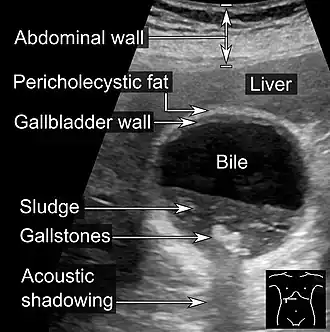

| Abdominal ultrasonography showing biliary sludge and gallstones | |

Biliary sludge refers to a viscous mixture of small particles derived from bile.[1][2] These sediments consist of cholesterol crystals, calcium salts, calcium bilirubinate, mucin, and other materials.[1][2][3]

Biliary sludge is typically diagnosed by CT scan or transabdominal ultrasonography.[1][2] Endoscopic ultrasonography is another more sensitive option. However, the gold standard is considered to be direct microscopy of aspirated gallbladder bile.[1][2] This method is much more sensitive, although it is less practical.[2]